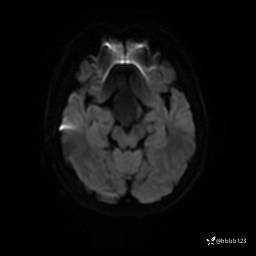

DWI: